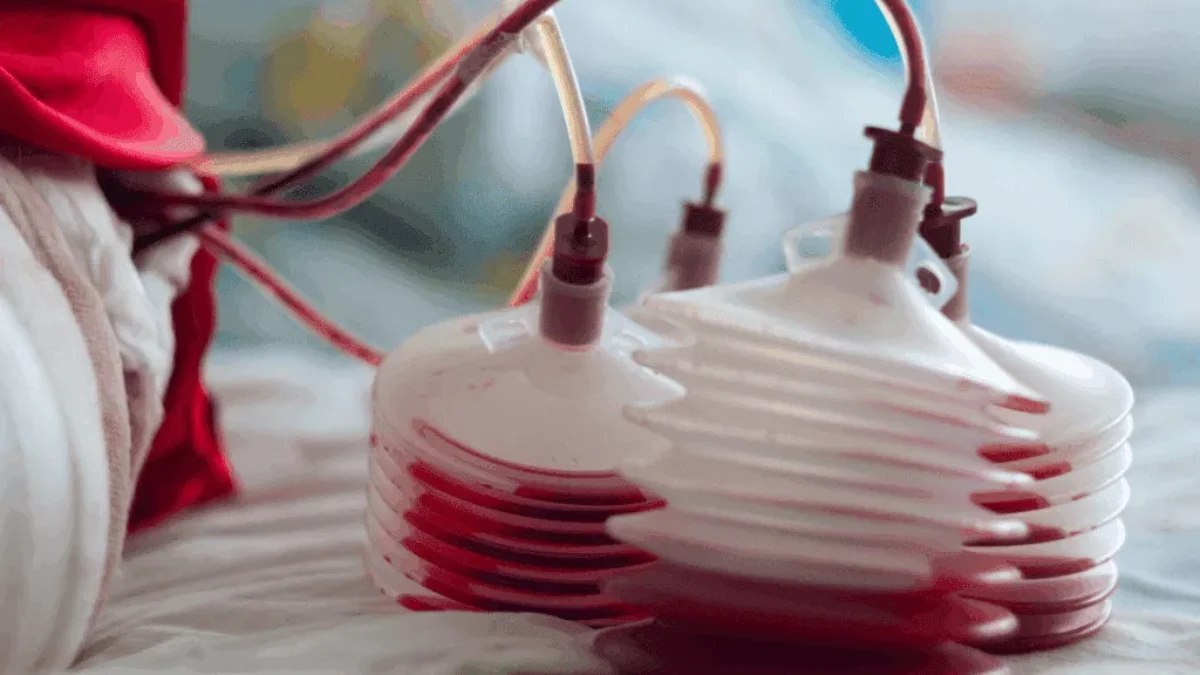

- احتمال بستری شدن نوزاد در قسمت مراقبتهای ویژه